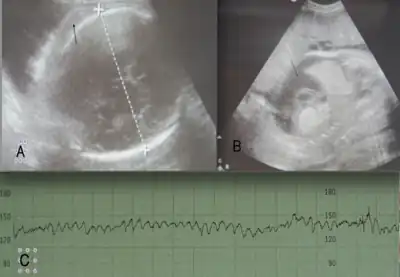

- Once the titer of anti-D reaches a certain threshold (normally 8 to 16), serial Ultrasound and Doppler examinations are performed to detect signs of fetal anemia

- Detection of increased blood flow velocities in the fetus are a surrogate marker for fetal anemia that may require more invasive intervention

- If the flow velocity is found to be elevated a determination of the severity of anemia needs to ensue to determine if an intrauterine transfusion is necessary

- This is normally done with a procedure called percutaneous umbilical cord blood sampling (PUBS or cordocentesis) [19]